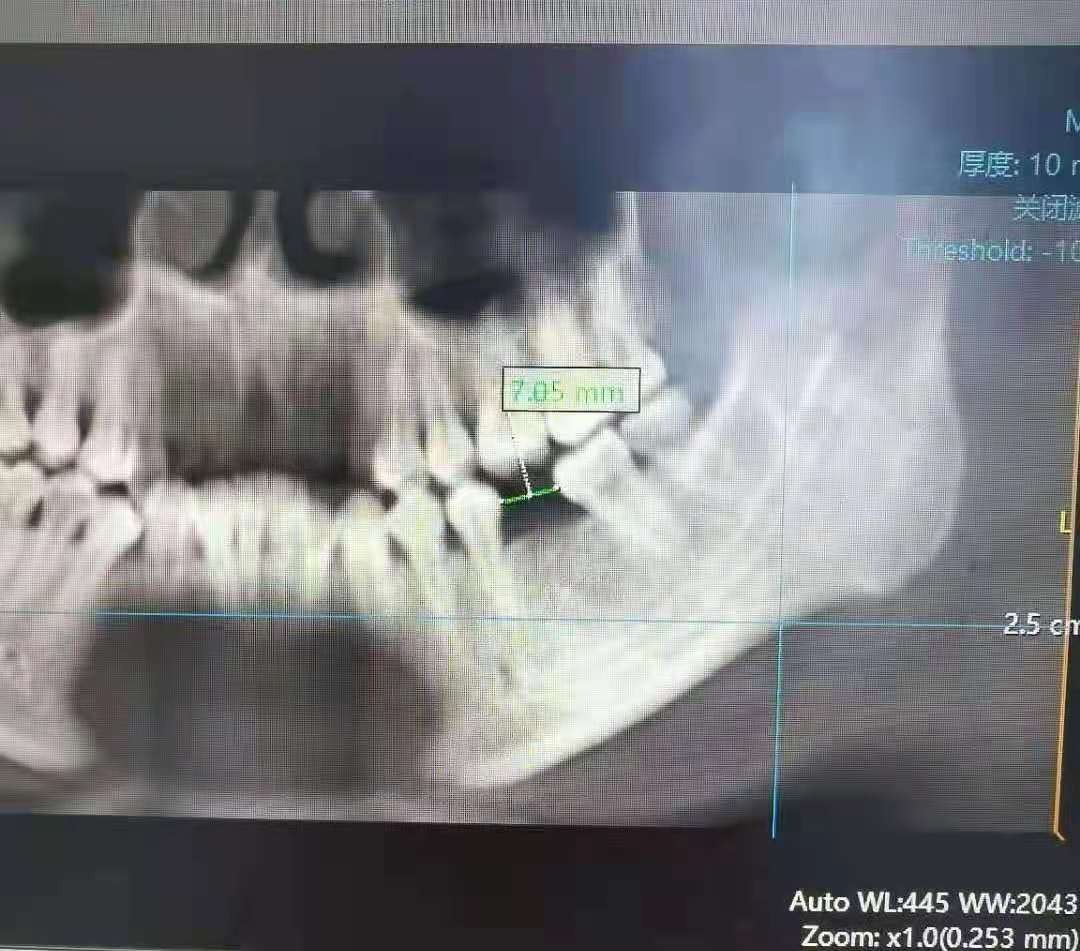

28岁的小然(化名),因左下大牙缺失到我院口腔门诊咨询就诊。经过口腔科张义仁医生的仔细检查,小然符合种植牙条件。通过对小然进行全身系统检查评估、口腔CBCT、模型分析等检查后,张医生为她进行种植体设计,并进行了术前沟通。手术中,医务人员严把无菌操作和手术流程关,让小然在无痛舒适的情况下顺利植入4×11mm种植体,整个过程安全、精准,为二期修复手术打下良好基础。

种植牙手术前后对比如图: